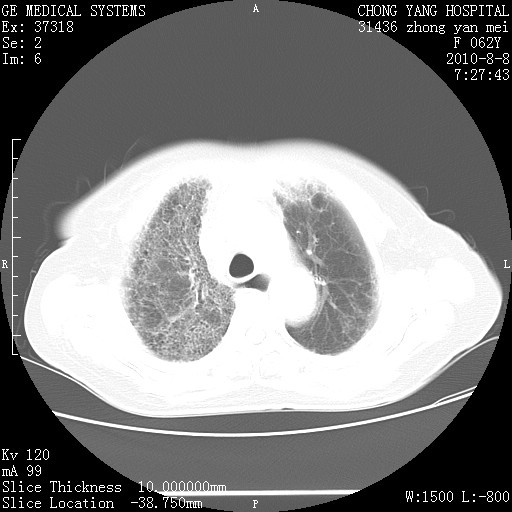

标题: CT28269:F62Y咳嗽胸痛数月。 [打印本页]

标题: CT28269:F62Y咳嗽胸痛数月。

两肺弥漫性间质纤维化伴继发性支扩。

考虑特发性肺间质纤维化

考虑两肺间质性肺炎并肺间质纤维化。

双肺间质纤维化合并感染、肺气肿

双肺间质纤维化

特发性的肺间质纤维化

两肺间质纤维化并牵拉性细支气管扩张。

考虑两肺间质性肺炎并肺间质纤维化,肺气囊形成。